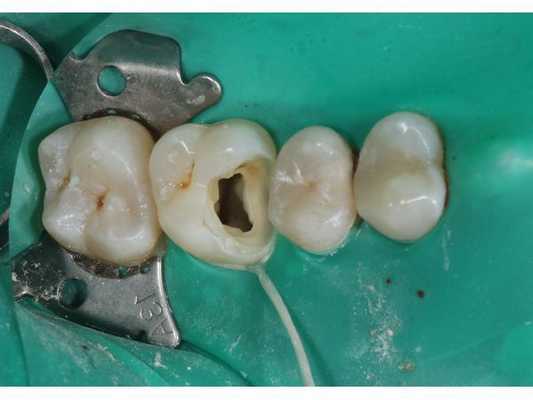

- Вскрытие полости зуба, формирование доступа к корневым каналам зуба 1.6.

- Механическая экстирпация (удаление) коронковой части пульпы зуба 1.6.

- Удаление устьевой части пульпы зуба 1.6 инструментом Protaper universal SX.

- Обтурация (пломбирование) корневых каналов системой вертикальной конденсации BeeFill.

- Адгезивная подготовка зуба 1.6. Подразумевает подготовку поверхности твёрдых тканей зуба в зоне дефекта, чтобы обеспечить прочную связь стоматологических материалов с эмалью, дентином и цементом. Тотальное травление (нанесение кислоты для прочного сцепления стоматологических материалов): эмаль — 30 секунд, дентин — 15 секунд. Адгезив — OptiBond Solo.

- Композитная реставрация зуба 1.6 с применением реставрационного материала — Estelite flow quick OA2, Estelite Sigma quick OA2.